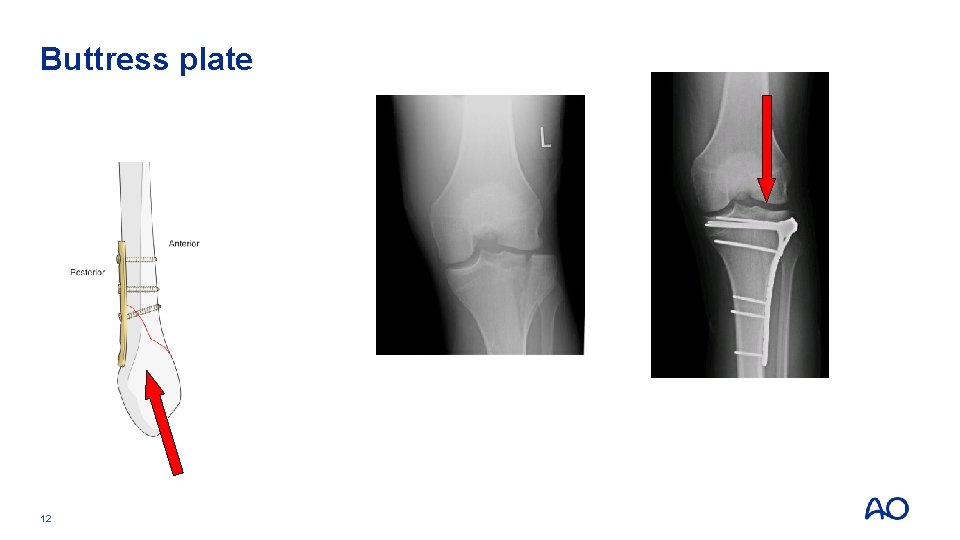

Buttress plate • Resists axial shear load by applying opposing force • In areas where bone is not supported by the shaft, eg, condyles 11 • Distal femur • Tibial plateau • Ankle

Buttress plate 12